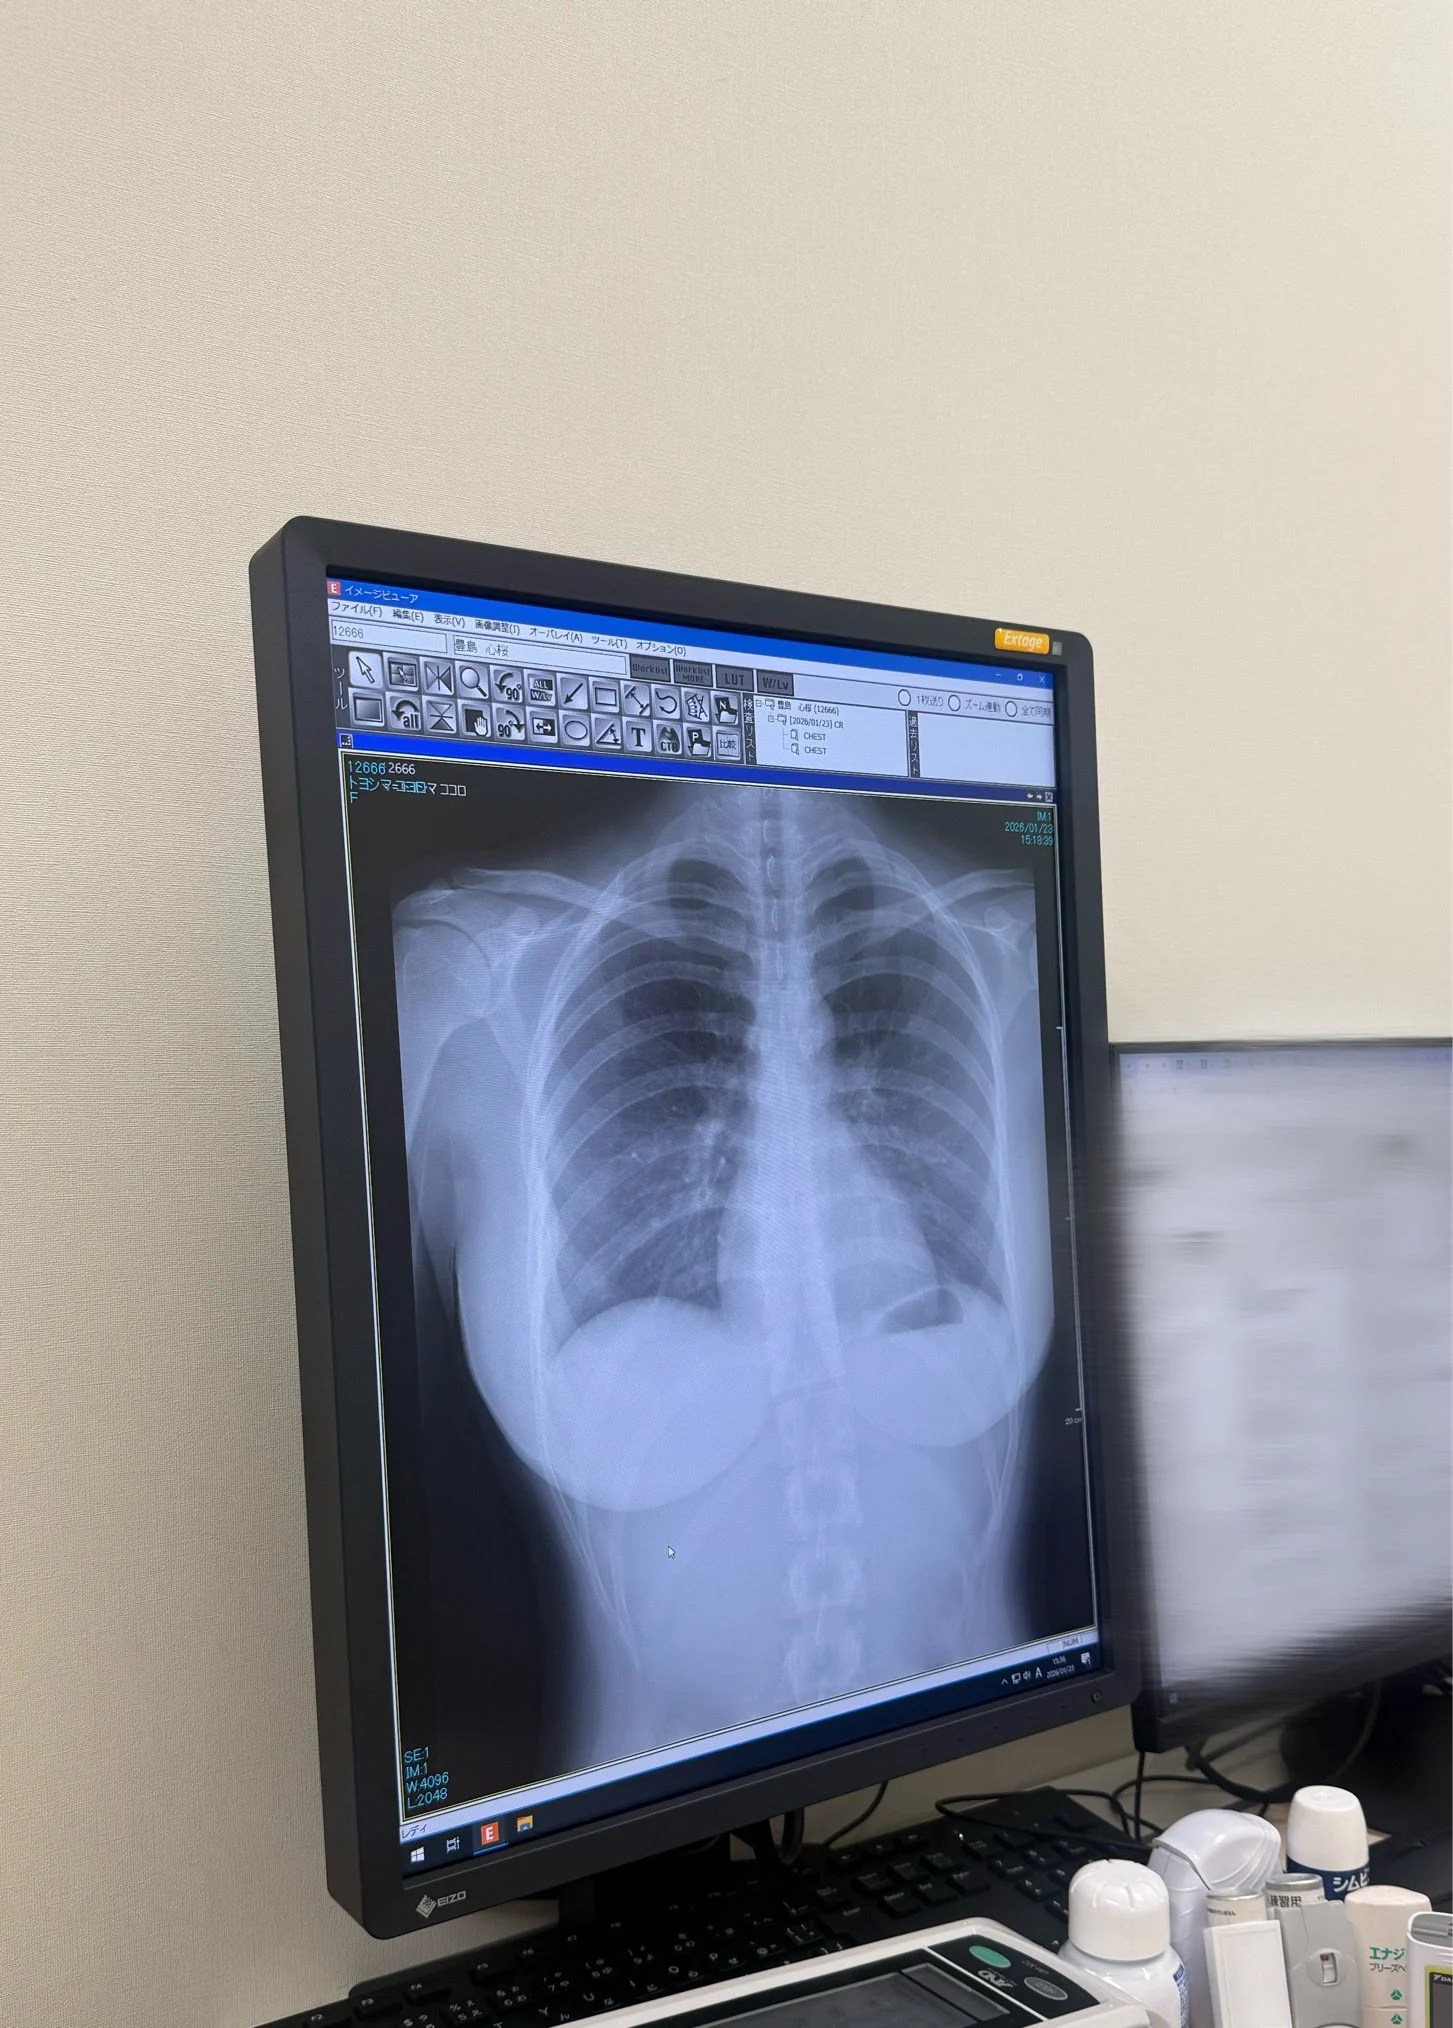

确实已经成为新潟県五泉市观光大使,也有主持着广播节目MBSラジオ「オレたちゴチャ・まぜっ!〜集まれヤンヤン〜」,常常跟不同艺人接触的「丰岛心樱」人缘极好,有时也挺幽默,这次竟然突然公开了自己的肺部X光照!

如此赤裸的表现也让粉丝们很惊喜:

「这张胸部正位X光片显示肺部状况极佳。双肺野清晰,未见浸润、结节或胸腔积水。心脏轮廓正常,胸廓骨骼未见骨折或异常。」

而且很少会有日本的写真偶像直接公开自己的X光片,一个是碍于医疗法的问题,另外一个是专业人士可以透过X光片确认是否是天然、没有经过整形的胸部哦!